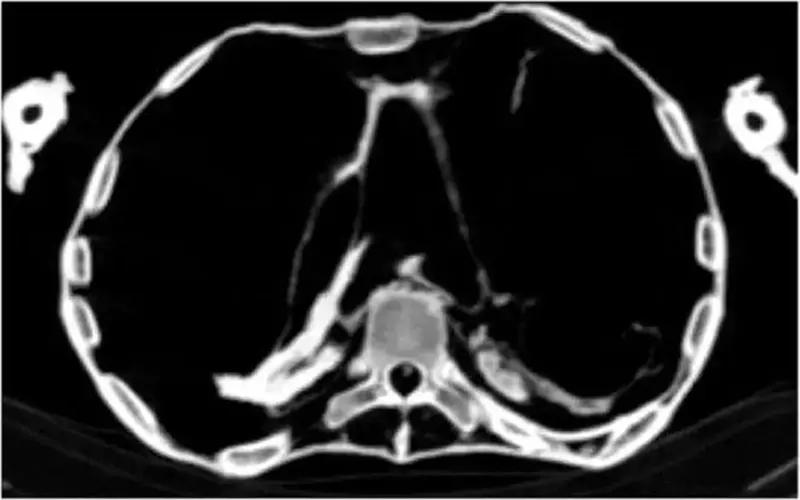

Mısır'da arkeologlar ve radyologlar tarafından yürütülen araştırma sonunda, 'çığlık atan mumya' olarak bilinen Mısırlı prensesin 3 bin yıl önce kalp krizi nedeniyle yaşamını yitirdiği belirlendi. Prensesin damar sertleşmesi ve koroner kalp hastalığından mustarip olduğu ve bunun sonucunda ani bir şekilde yaşamını yitirdiği belirtildi.

Uzmanlar, mumyalarda damar tıkanıklığı bulgularına ulaştı.